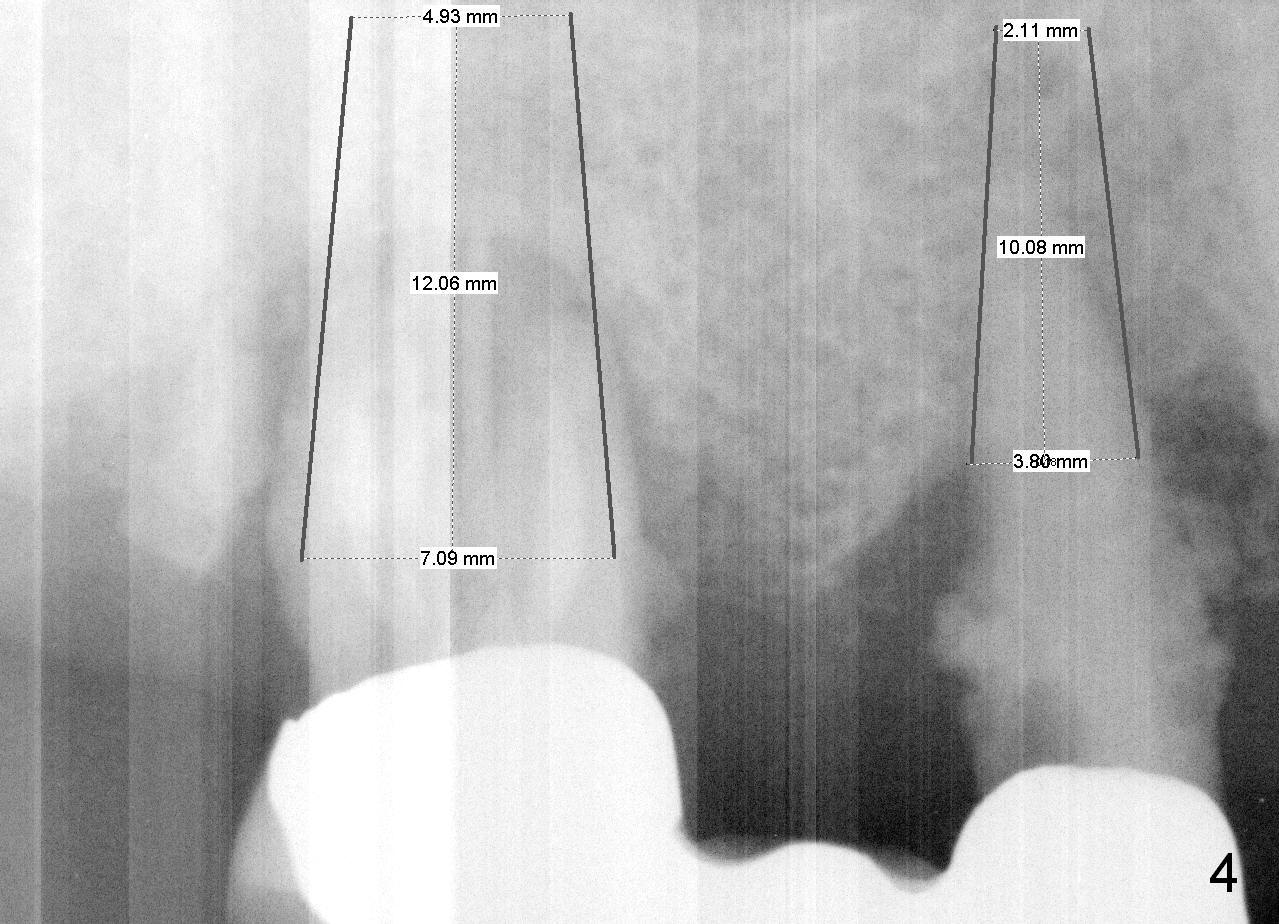

A 78-year-old lady (YT) has had poor dentition. The tooth #2 fractured 3 years ago (Fig.1). Now bone loss around the abutments for the bridge at #3-5 is more severe (Fig.2). There is an abscess palatal to the tooth #5. After extraction, the socket at #3 should be large (treated with 2% Xylocaine/1:50,000 Epinephrine). An extra wide implant is expected. Since there is more than 12 mm of bone in height (Fig.3), a UF implant is the most appropriate (6, 6.5 or 7x12 mm, Fig.4). The longest extra wide SM implant is 10 mm.